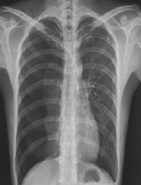

| 病史:男性,65歲,活動后胸悶6個月。既往高血壓病史15年。診斷: |

| ○ 靴型心 | |

| ○ 梨形心 | |

| ○ 普大型心臟 | |

| ○ 正常心臟 | |

| ○ 以上均不是 |